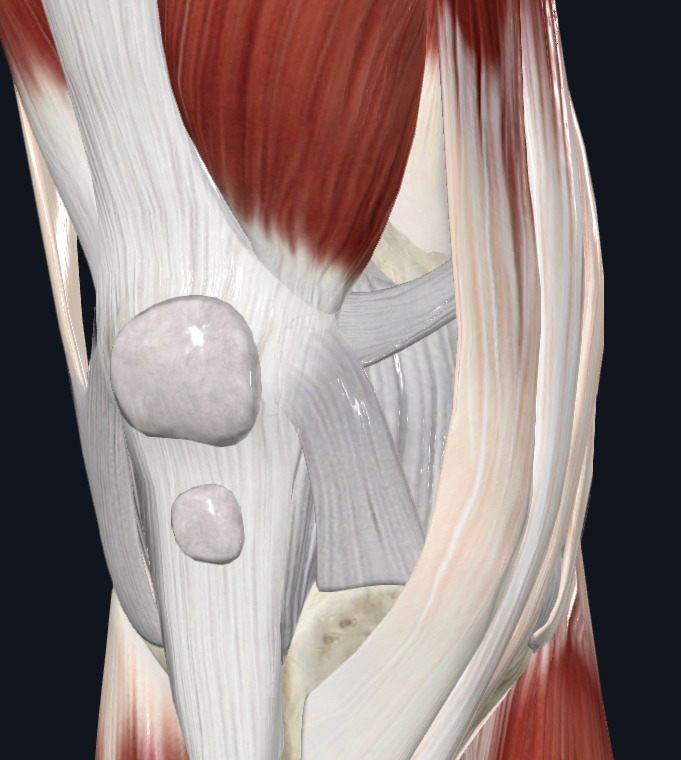

사진설명 - 무릎관절의 구조물을 보여주고 있다.

관절 속에 음압력을 구조는 힘줄, 인대, 관절와 등등이 존재하는데 우리가 능동적인 조절이 가능한 것은 근육이다.

여기서 필자가 말하고자 하는 것은 어떻게 하면 퇴행성 관절염을 “예방” 할 수 있느냐 이다.